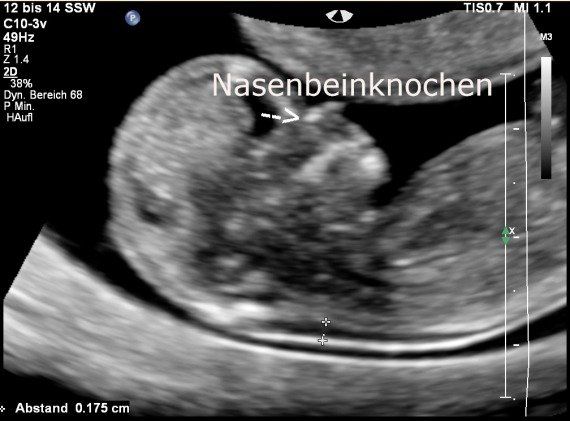

Unten: Messung der Nackentranparenz; Oben: der Pfeil weist auf den Nasenbeinknochen

Ein Kriterium betrifft das fetale Nasenbein. Der Nachweis dieses Knochens gelingt bei chromosomal normalen Feten im Untersuchungszeitraum der Nackentransparenzmessung nur in ungefähr 2 % der Fälle nicht, bei Feten mit Trisomie 21 kann man ihn in 65 % der Fälle nicht darstellen.